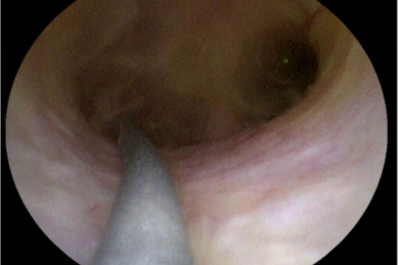

鼻内镜「精准拆弹」,中大医院专家微创切除颅底脊索瘤